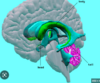

Label A-E

A: **caudate nucleus** B: **internal capsule** C: **putamen** D:**globus pallidus** E: **subthalamic nuclei**